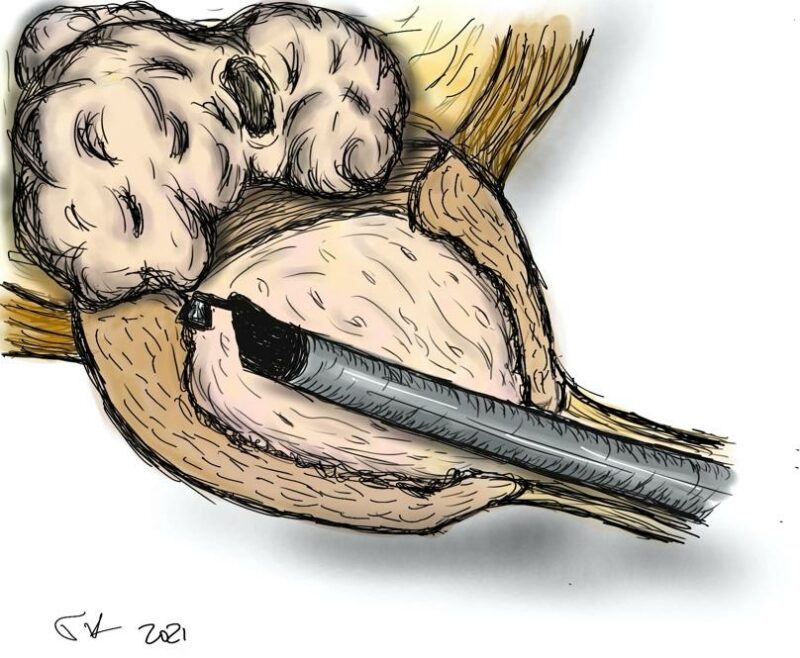

- το προστατικό αδένωμα αποκολλάται από την κάψα με τη βοήθεια του ειδικού ηλεκτροδίου εκπυρήνισης (εικόνες 1-4)

Εικόνες 1-4